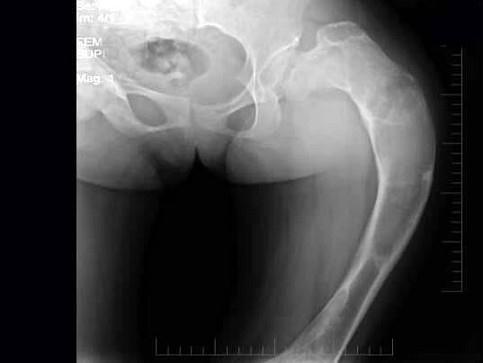

问题 女,17岁,左髋部酸胀不适半年,骨盆正位片如图所示,最可能的诊断是?(?)

选项 A.骨髓炎 B.内生软骨瘤 C.骨纤维结构不良 D.骨斑点症 E.以上均不正确

答案 C